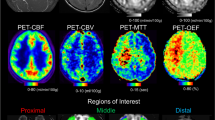

Quantitative perfusion analysis

ASL-CBF, DSC-CBF, and DSC-TTP maps were co-registered with the 3D T1-weighted anatomical sequence by a linear registration process using the FMRIB Linear Image Registration Tool of FSL v.6 [20]. For quantitative analysis, an atlas-based segmentation of the MCA vascular territory was performed for each brain hemisphere, creating a single volume of interest resulting from the merger of proximal, intermediate, and distal MCA flow territory ROIs, as reported by Mutsaerts et al. [21]. Quantitative perfusion assessment was performed across the voxels of the MCA vascular territory of each hemisphere at each time point using the fslstats function of FSL, measuring the mean values and standard deviation of the three perfusion parameters, i.e., (i) ASL-CBF, (ii) DSC-CBF, (iii) and DSC-TTP. The ASL-sCoV was then calculated at each time point as ASL-CBF standard deviation/ASL-CBF mean × 100. ASL-sCoV generates one value per ROI, with higher values indicating greater spatial heterogeneity [13]. The non-treated hemispheres of the patients who underwent unilateral revascularization were excluded from the analysis.

Table 2 reports mean values of ASL and DSC perfusion parameters in MCA territories at each time point. Over time, different temporal variations of CBF parameters were observed depending on the type of MR perfusion technique. In particular, a gradual and significant increase in DSC-CBF values was observed in MCA territories after surgery (P < .001). Conversely, only a trend of reduction was observed for ASL-CBF values 6 months after surgery followed by progressive increase of mean values from the 12th month onwards in the MCA territories (P = .088) (Fig. 2). Accordingly, the Bland-Altman plot analysis (Fig. 3a) revealed poor agreement between ASL-CBF and DSC-CBF in preoperative perfusion examinations (bias 9.8 mL/min/100 g; limits of agreement 23.9 and − 4.3 mL/min/100 g) with gradual improvement after surgery (from bias 3.5 mL/min/100 g at 6 months to bias − 0.6 mL/min/100 g at 24 months) (Fig. 3b–d). On the other hand, ASL-sCoV and DSC-TTP showed similar significant progressive reduction after surgery (Fig. 4). Additionally, before surgery, DSC parameters (i.e., CBF and TTP) showed moderate-to-strong correlation only with ASL-sCoV values (r2 = − 0.562, P < .001 for DSC-CBF; r2 = 0.535, P = .001 for DSC-TTP), while ASL-CBF correlated with DSC perfusion parameters exclusively in postoperative perfusion examinations (Fig. 5).

Serial MR angiography and perfusion studies in a patient with left moyamoya vasculopathy treated with EDAMS. White arrowheads indicate post-surgical development of pial collateralization in the site of surgical revascularization. Progressive DSC-TTP reduction and ASL-CBF improvement occurred in the middle cerebral artery territory after surgery (empty white arrows). Note the lower spatial variation of ASL label in late post-surgical maps due to the reduction of arterial transit artifacts (white arrows) with the improvement of arterial transit time. Color bar indicates seconds and mL/min/100 g for DSC-TTP and ASL-CBF, respectively

Serial MR angiography and perfusion studies in a patient with left moyamoya vasculopathy treated with EDAMS and not improved vascularization after surgery. White arrowheads indicate the site of surgical revascularization. The thin white arrow indicates left parietal region with reduced number of distal branches of middle cerebral artery in the later stages after surgery. No significant improvement of DSC-TTP and ASL-CBF occurred in the middle cerebral artery territory after surgery (empty white arrows indicate high DSC-TTP and low ASL-CBF at different levels of middle cerebral artery territory). Note the high spatial variation of ASL label in pre- and post-surgical maps due to the presence of arterial transit artifacts (thick white arrows). Color bar indicates seconds and mL/min/100 g for DSC-TTP and ASL-CBF, respectively